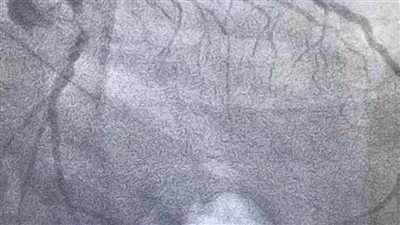

تركيب دعامة

"صحة الدقهلية": تركيب ٣ دعامات لمريض يعاني من انسداد بالشريان

لبنان : الحريري يعود إلى بيروت بعد خضوعه لقسطرة وتركيب دعامة في القلب